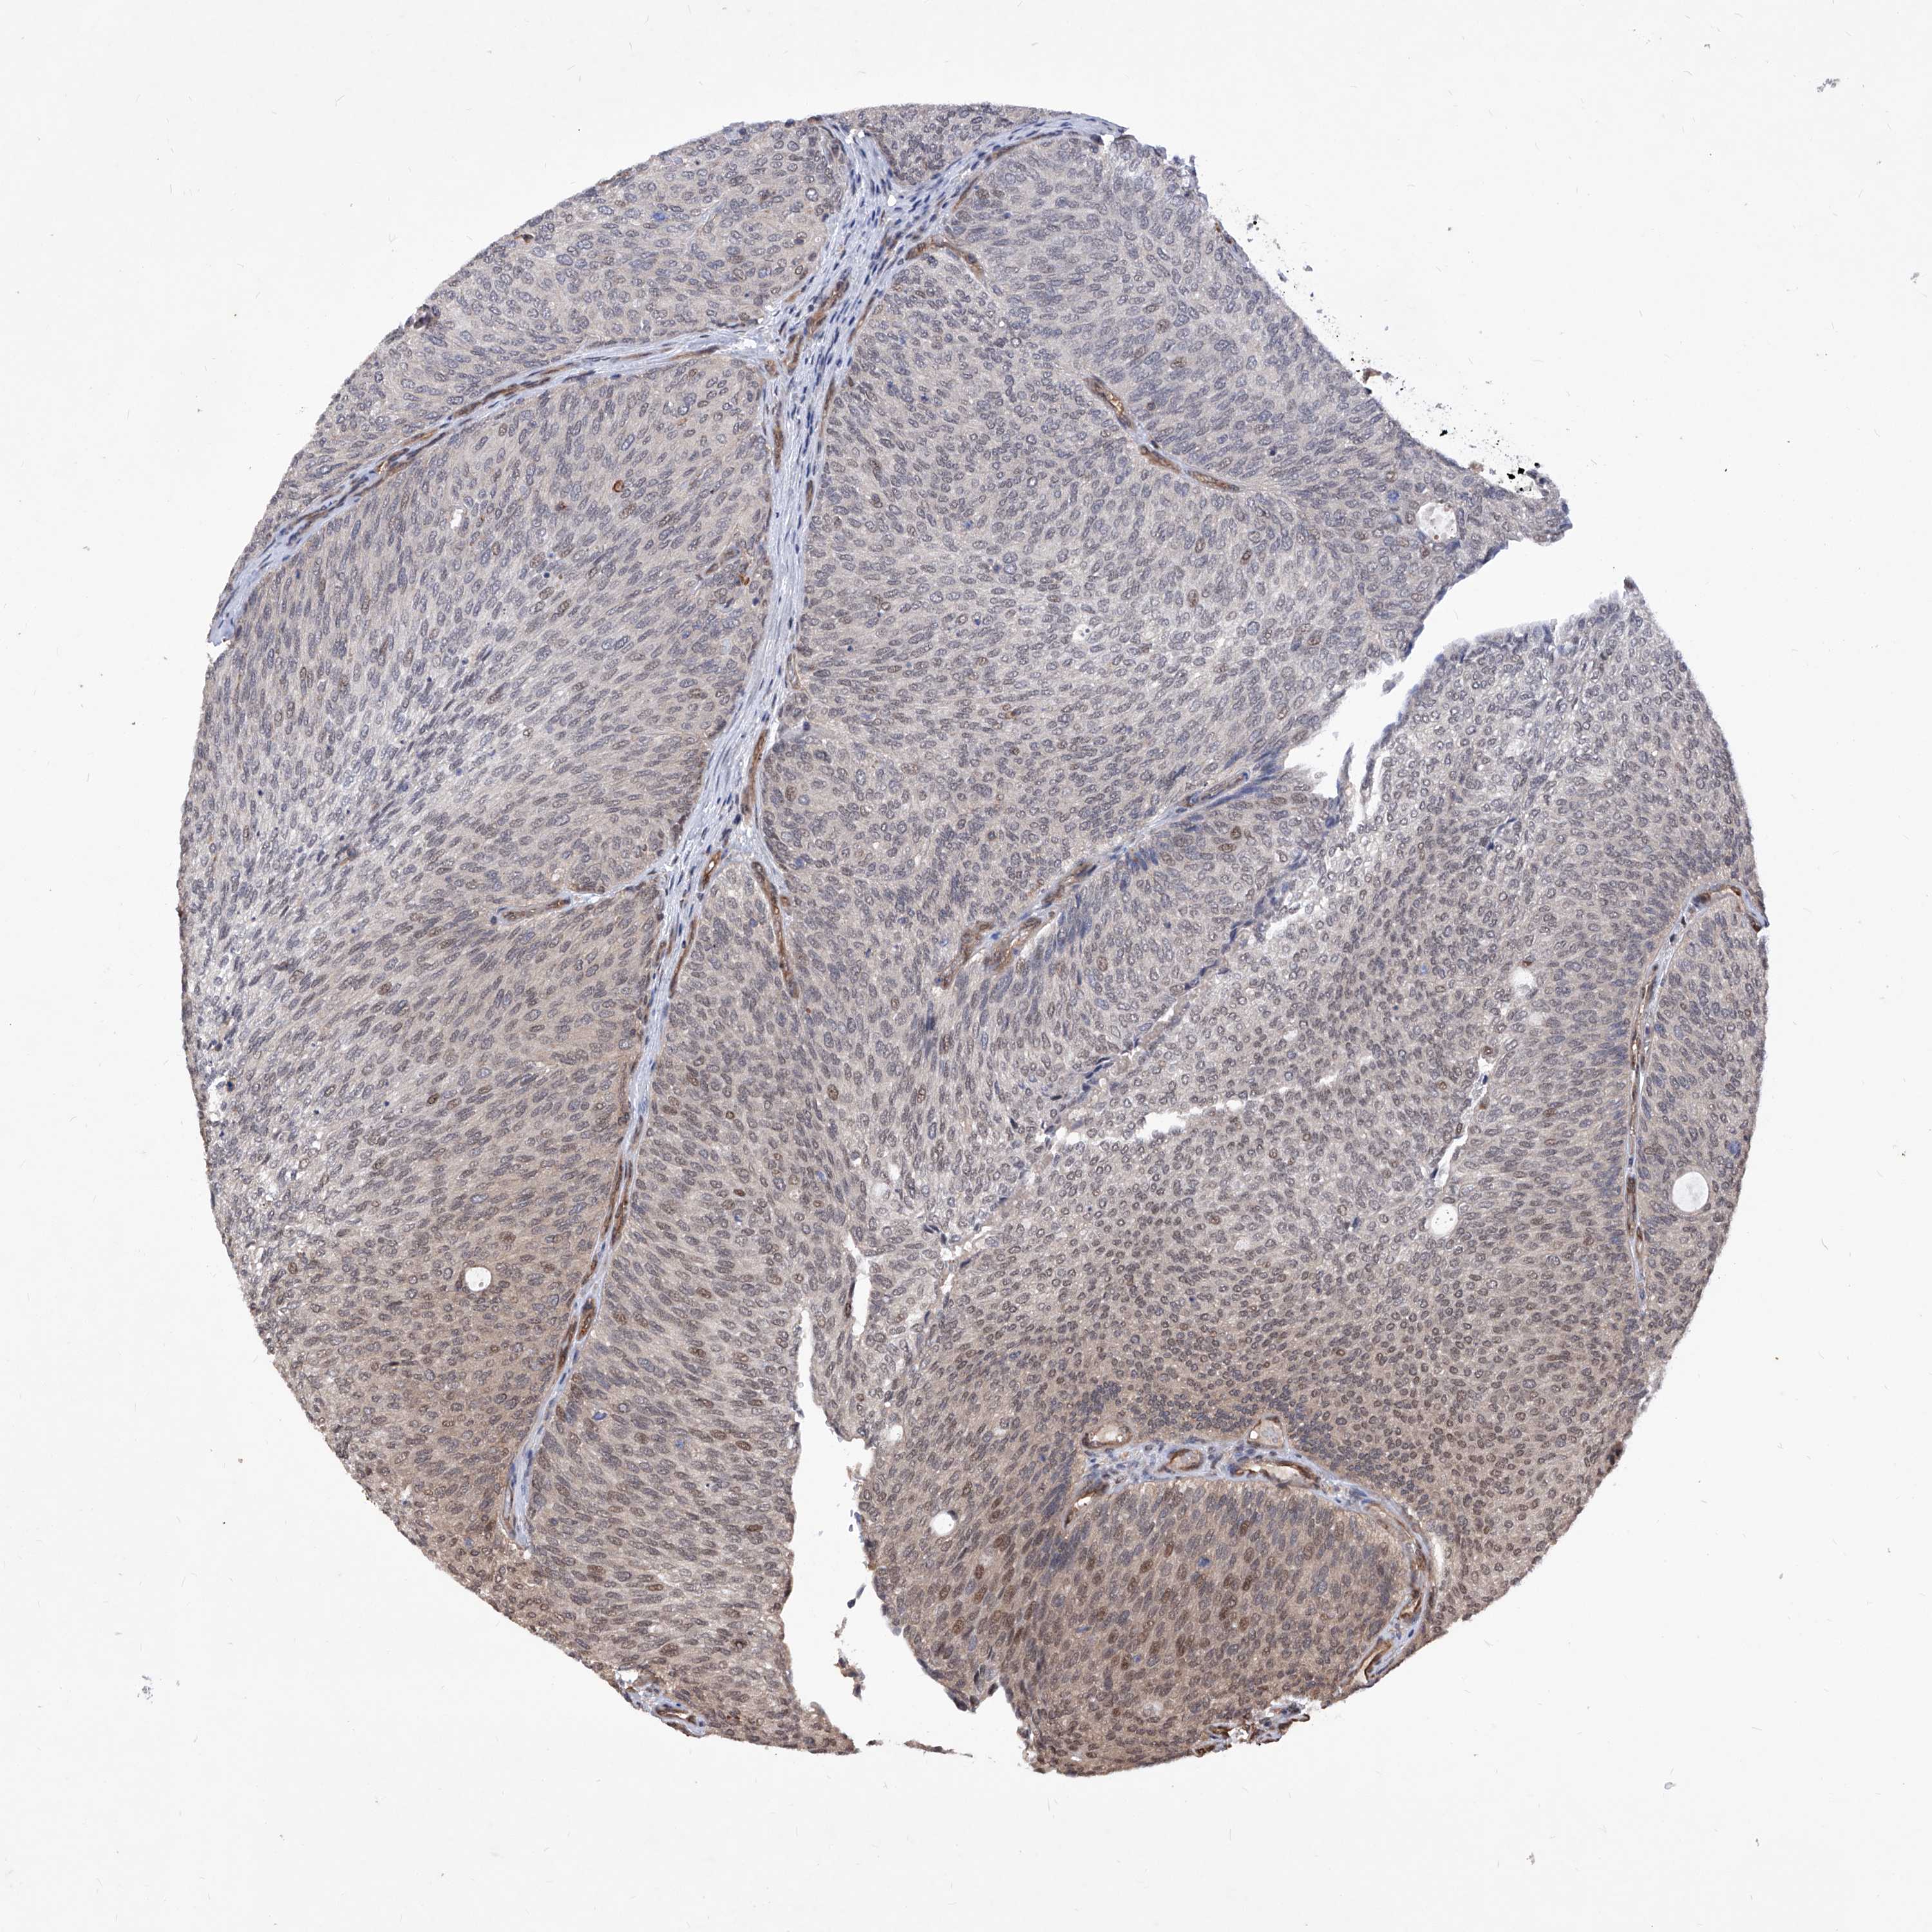

UROTHELIAL CANCER - Protein expressioni

A mouse-over function shows sample information and annotation data. Click on an image to view it in a full screen mode. Samples can be filtered based on level of antibody staining by selecting one or several of the following categories: high, medium, low and not detected. The assay and annotation is described here.

Note that samples used for immunohistochemistry by the Human Protein Atlas do not correspond to samples in the TCGA dataset.

Antibody stainingi

Antibody staining in the annotated cell types in the current human tissue is reported as not detected, low, medium, or high, based on conventional immunohistochemistry profiling in selected tissues. This score is based on the combination of the staining intensity and fraction of stained cells.

Each image is clickable and will lead to virtual microscopy that enables deeper exploration of all samples and also displays staining intensity scores, fraction scores and subcellular localization as well as patient and tissue information for each sample.

Antibody HPA029534

Staining

High

Medium

Low

Not detected

Intensity

Strong

Moderate

Weak

Negative

Quantity

>75%

75%-25%

<25%

None

Location

Nuclear

Cytoplasmic/membranous

Cytoplasmic/membranous,nuclear

Urothelial carcinoma, Low grade

Urothelial carcinoma, High grade